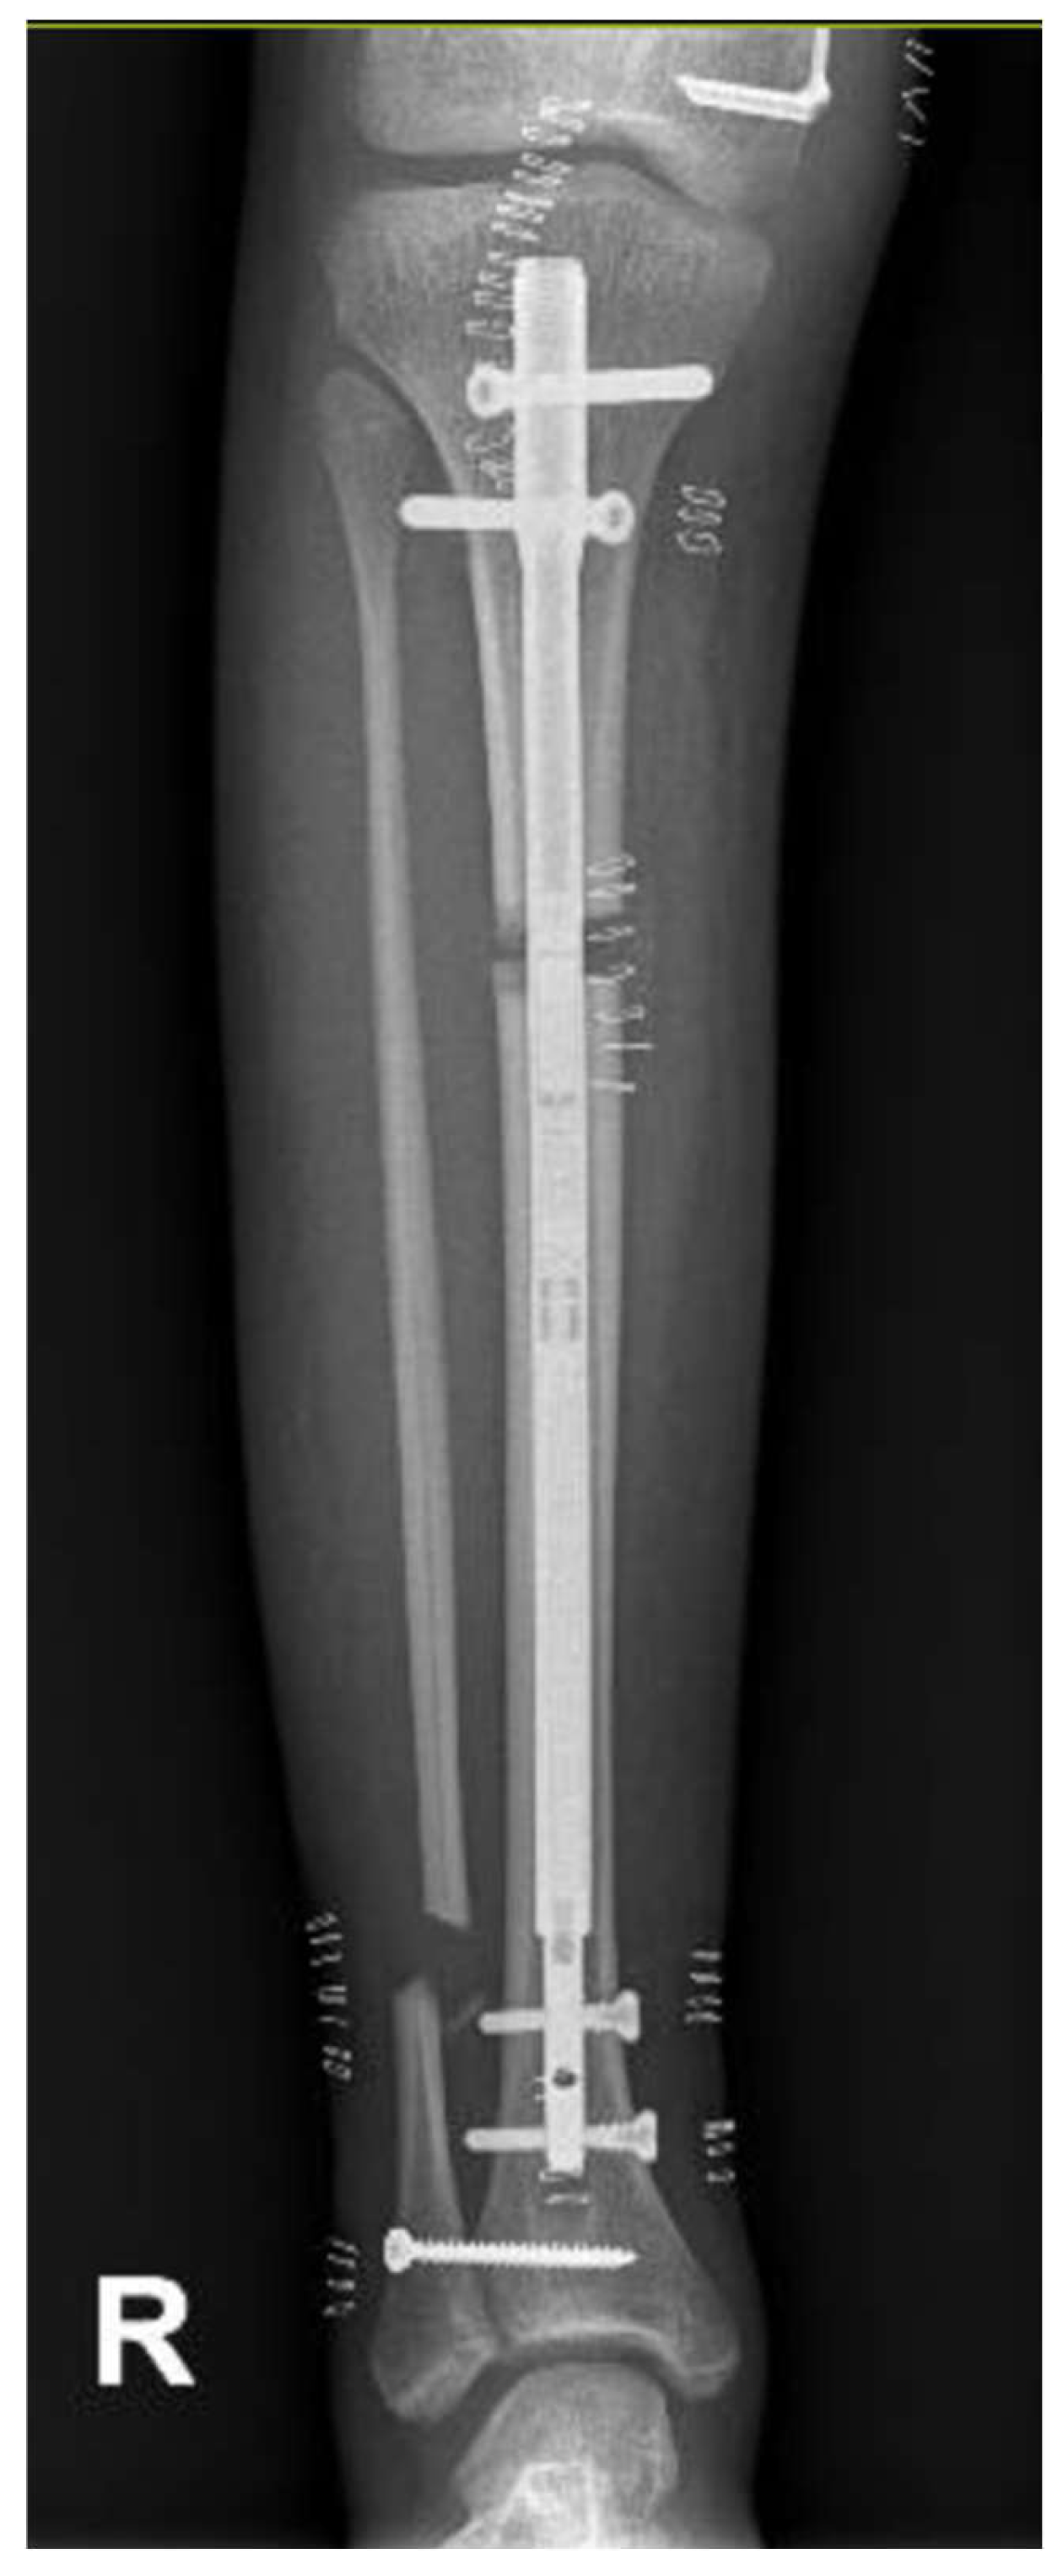

The patient presented to our attention at about 6 months post-surgery complaining of acute pain and deformity at the middle third of the thigh. Radiographs showed fracture of the femoral regenerate (Figure 4). The patient underwent immediate external fixator removal, reduction of the knee dislocation and finally Elastic Stable Intramedullary Nailing (ESIN) of the femoral fracture prior attempt to ream the femoral canal losing 20 of the 60 mm lengthened (Figure 5). Ten months after the procedure, the patient underwent nail removal for complete fracture consolidation.

At the age of 11, due to the persistent right femoral deficiency, the patient underwent temporary distal femur epiphysiodesis of the left lower limb thus allowing the length of the two femurs to be evened out in just over 2 years. Finally at the age of 14, due to the residual tibial hypoplasia (≅ 40 mm) and valgus knee (Figure 6), she underwent a proximal right tibial osteotomy and placement of an antegrade PRECICE® expandable intramedullary nail and temporary femoral distal medial emiepiphysiodesis (Figure 7) (Figure 8).